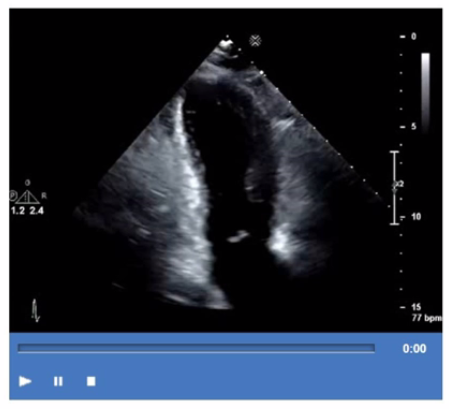

Which view is best for assessing atrial situs in the presence of congenital heart disease?

The subcostal view is the preferred transthoracic echocardiographic window to assess atrial situs, especially in congenital heart disease. This view provides a cross-sectional look at the abdominal organs and atrial chambers, helping determine the relative position of the inferior vena cava and aorta, which aids in defining atrial situs (solitus, inversus, or ambiguous).

Short axis and long axis views provide excellent cardiac anatomy but are less informative for visceral situs. The suprasternal notch window is mainly used to visualize the great vessels but does not provide adequate assessment of atrial situs.